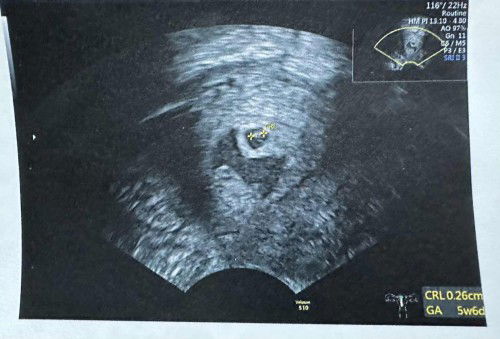

สอบถามหน่อยได้ไหมคะแม่ๆ อันนี้คือน้องหลุดใช่ไหมคะ

#ขอบคณสำหรับคำตอบล่วงหน้านะคะ